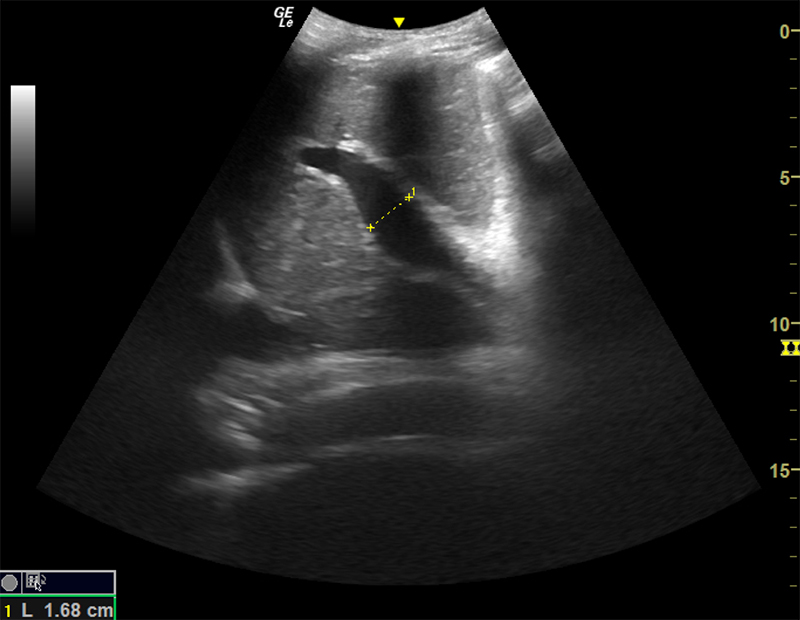

- Size of liver

- 12-14 cm in sagittal antero-posterior dimension at mid-clavicular line. 15

- <16 cm from posterior superior to anterior inferior.13

Figure 11. Normal Liver as seen from the right flank coronal view. Note the smooth surface, fine homogenous texture, and tubular vascular structures. The normal anterior-posterior diameter in the mid-clavicular line sagittal plane is between 12-14cm (A). The normal maximum dimension is from anteroinferior to posterosuperior is <16cm (B).